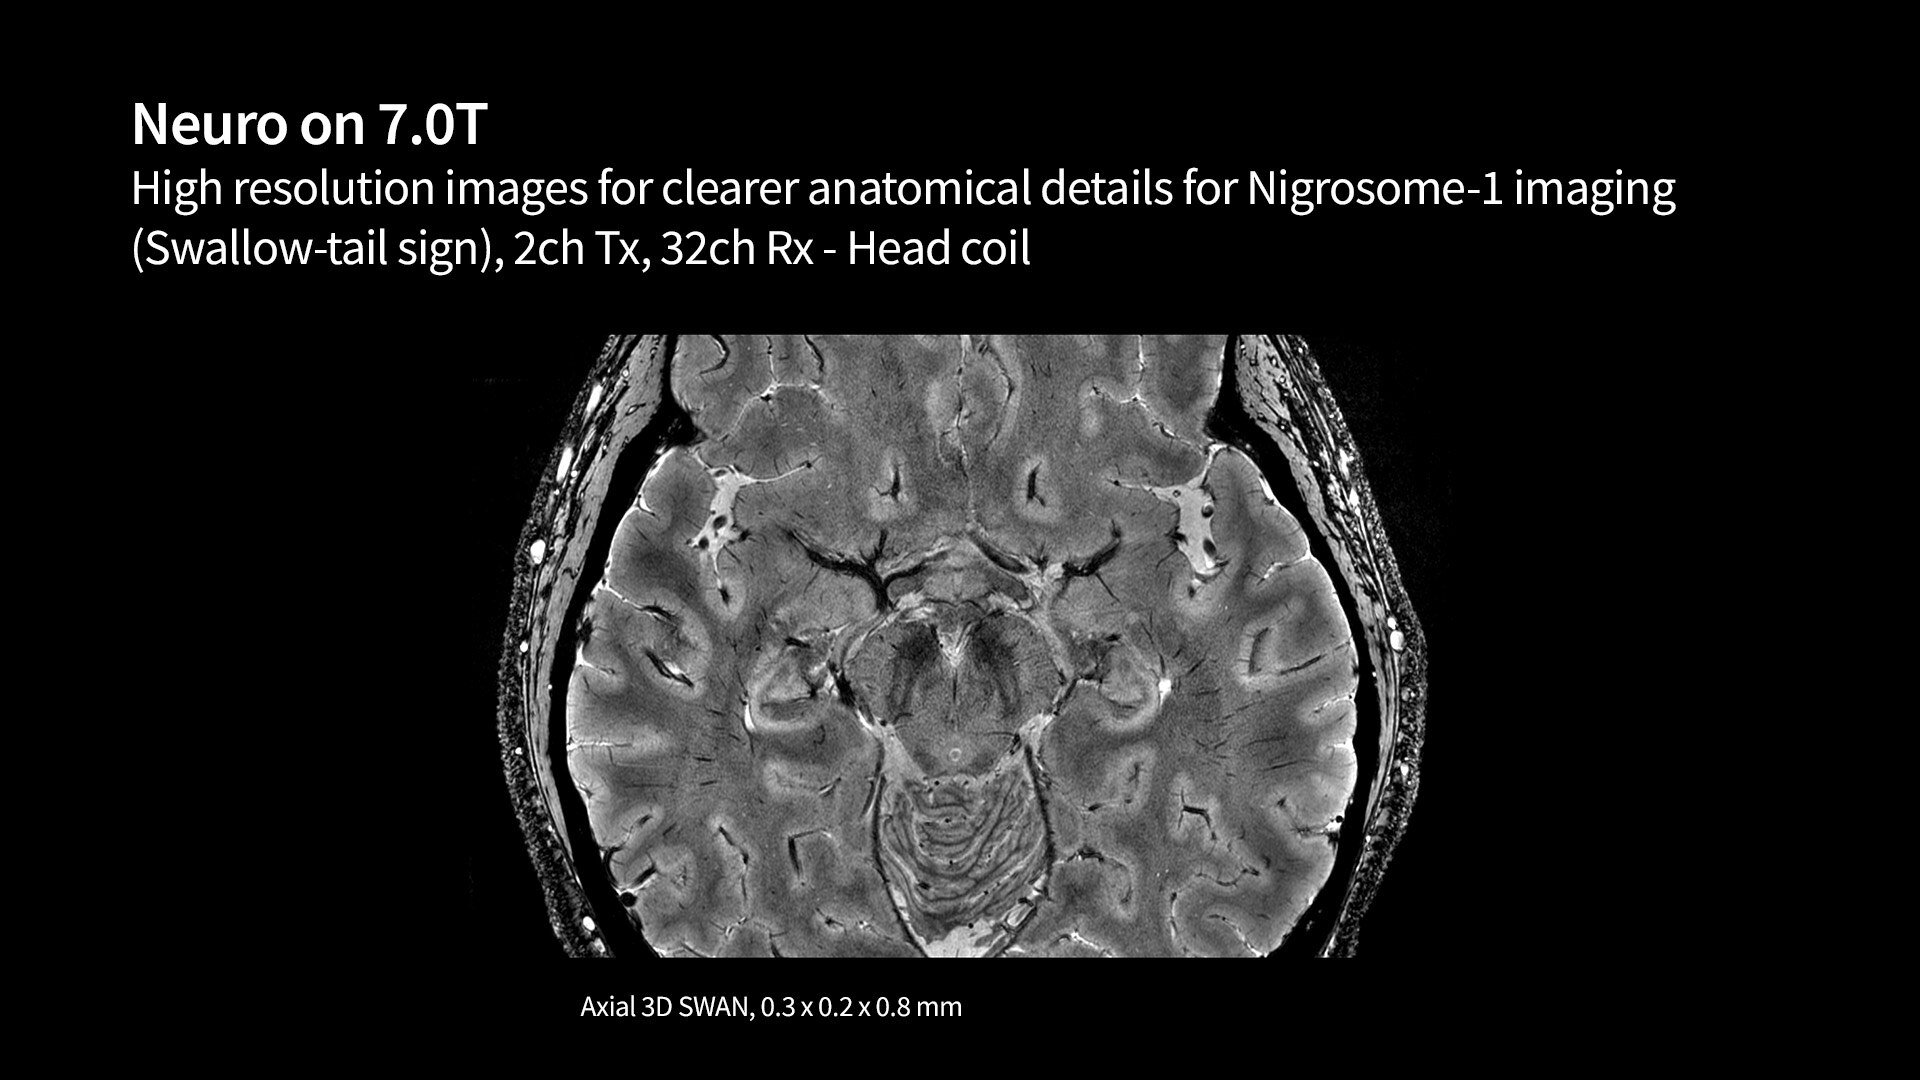

Groundbreaking discoveries and partnerships that elevate population outcomes

We are helping enable groundbreaking discoveries with a wide array of research-focused MR technology. This technology is opening up research and new care pathways to better understand the world's most debilitating diseases like cancer, as well as neurodegenerative, cardiovascular and psychological diseases. We hope to empower you with ongoing partnerships and continued AI innovation to discover new biomarkers that could lead to significant breakthroughs in your understanding of disease.